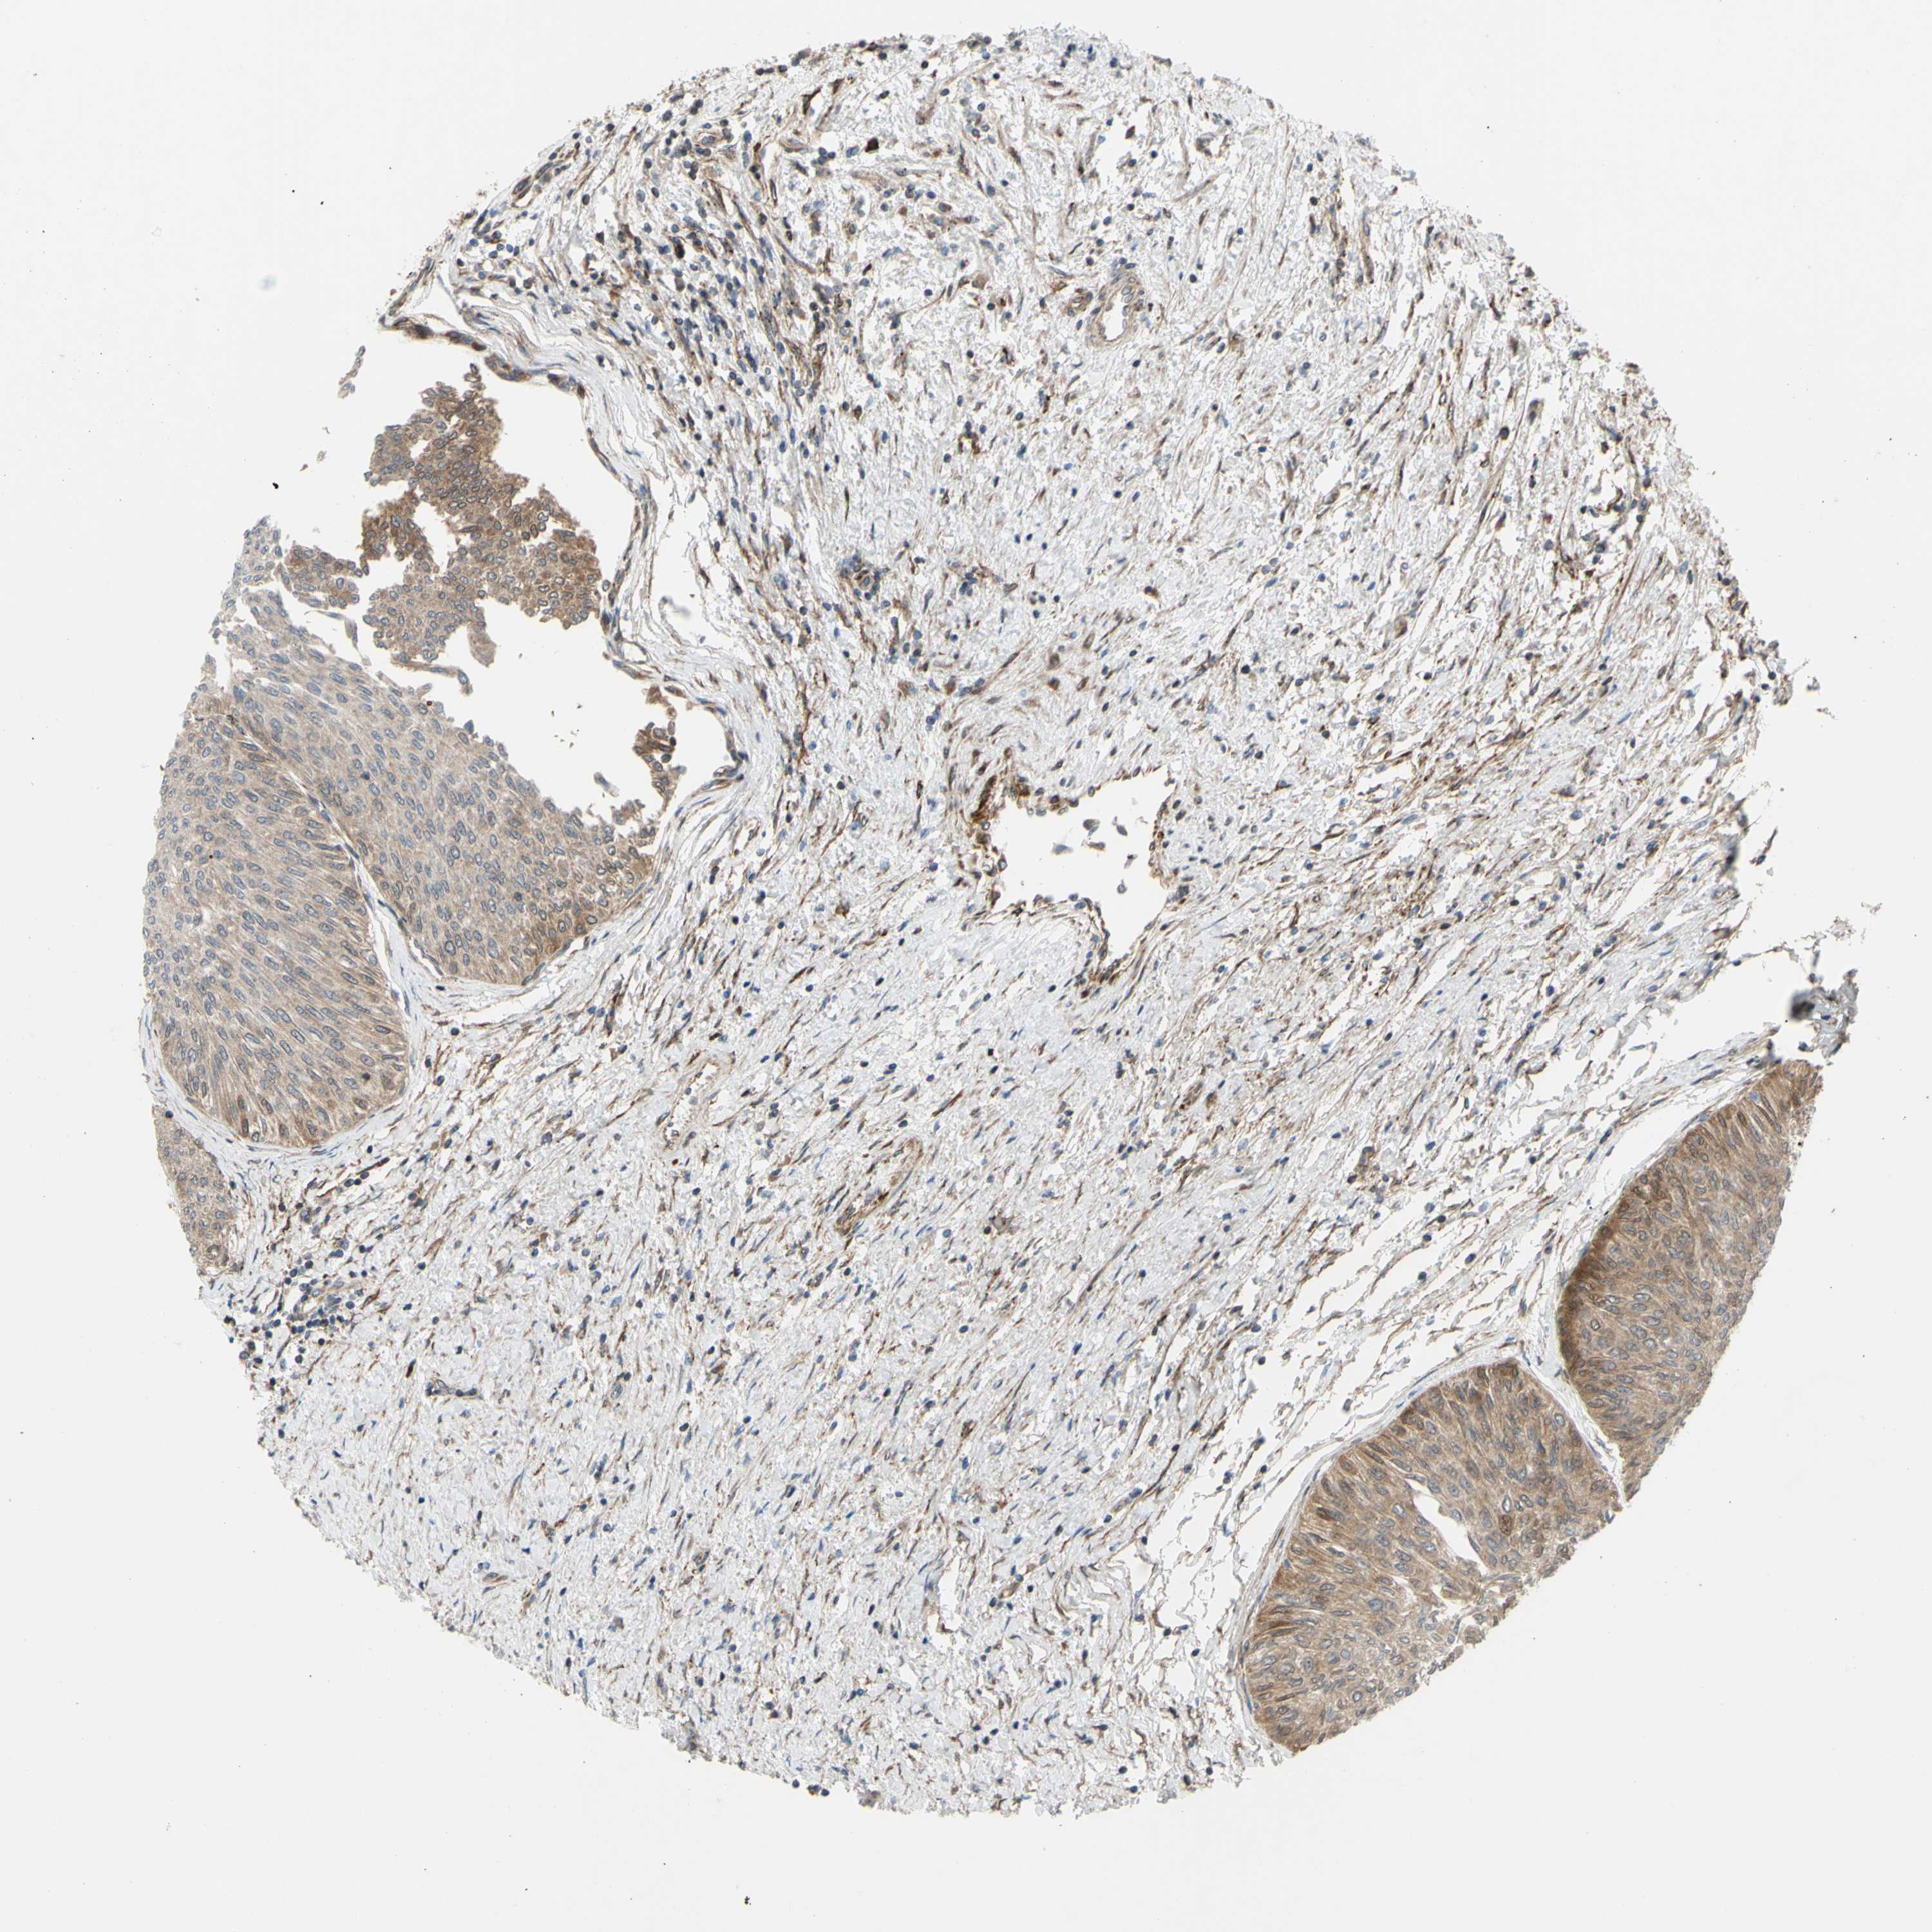

UROTHELIAL CANCER - Protein expressioni

A mouse-over function shows sample information and annotation data. Click on an image to view it in a full screen mode. Samples can be filtered based on level of antibody staining by selecting one or several of the following categories: high, medium, low and not detected. The assay and annotation is described here.

Antibody stainingi

Antibody staining in the annotated cell types in the current human tissue is reported as not detected, low, medium, or high, based on conventional immunohistochemistry profiling in selected tissues. This score is based on the combination of the staining intensity and fraction of stained cells.

Each image is clickable and will lead to virtual microscopy that enables deeper exploration of all samples and also displays staining intensity scores, fraction scores and subcellular localization as well as patient and tissue information for each sample.

Antibody HPA002859

Antibody CAB011655

Urothelial carcinoma, High grade

Urothelial carcinoma, Low grade

Adenocarcinoma, NOS